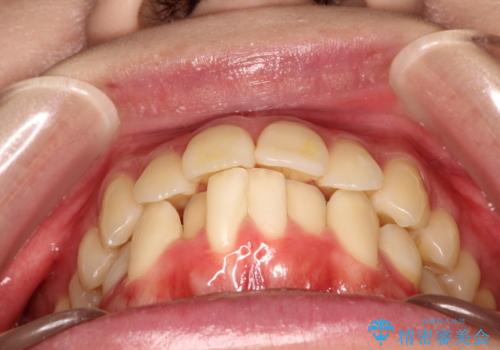

- 前歯が出ているため口が閉じにくく、横顔が気になるとのことで来院された患者様です。。

上下の前歯が前方に傾斜しており、口唇の突出感がありました。

上下左右の前から4番目の歯を抜歯して、上下の前歯を後方に移動させる計画としました。

抜歯矯正により、前歯をしっかり下げることで口元がすっきりしました。